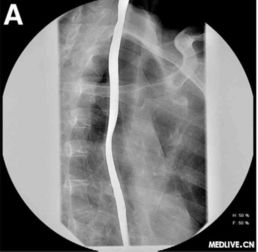

為了保證檢查準(zhǔn)確,做食道鋇餐檢查早晨不能吃飯喝水,包括肝功,血脂,血糖等檢查也是這樣要求的.X線鋇餐檢查 食管X線鋇餐檢查可顯示鋇劑在癌腫點(diǎn)停滯,病變段鋇流細(xì)窄;食管壁僵硬,蠕動(dòng)減弱,粘膜紋變粗而紊亂,邊緣毛糙;食管腔狹窄而不規(guī)則,梗阻上段輕度擴(kuò)張,并可有潰瘍壁龕及棄盈缺損等改變。

常規(guī)X線鋇餐檢查常不易發(fā)現(xiàn)淺表和小癌腫。應(yīng)用甲基纖維素鈉(sodium methyl cellulose)和鋇劑作雙重對(duì)比造影,可更清楚地顯示食管粘膜,提高食管癌的發(fā)現(xiàn)率。